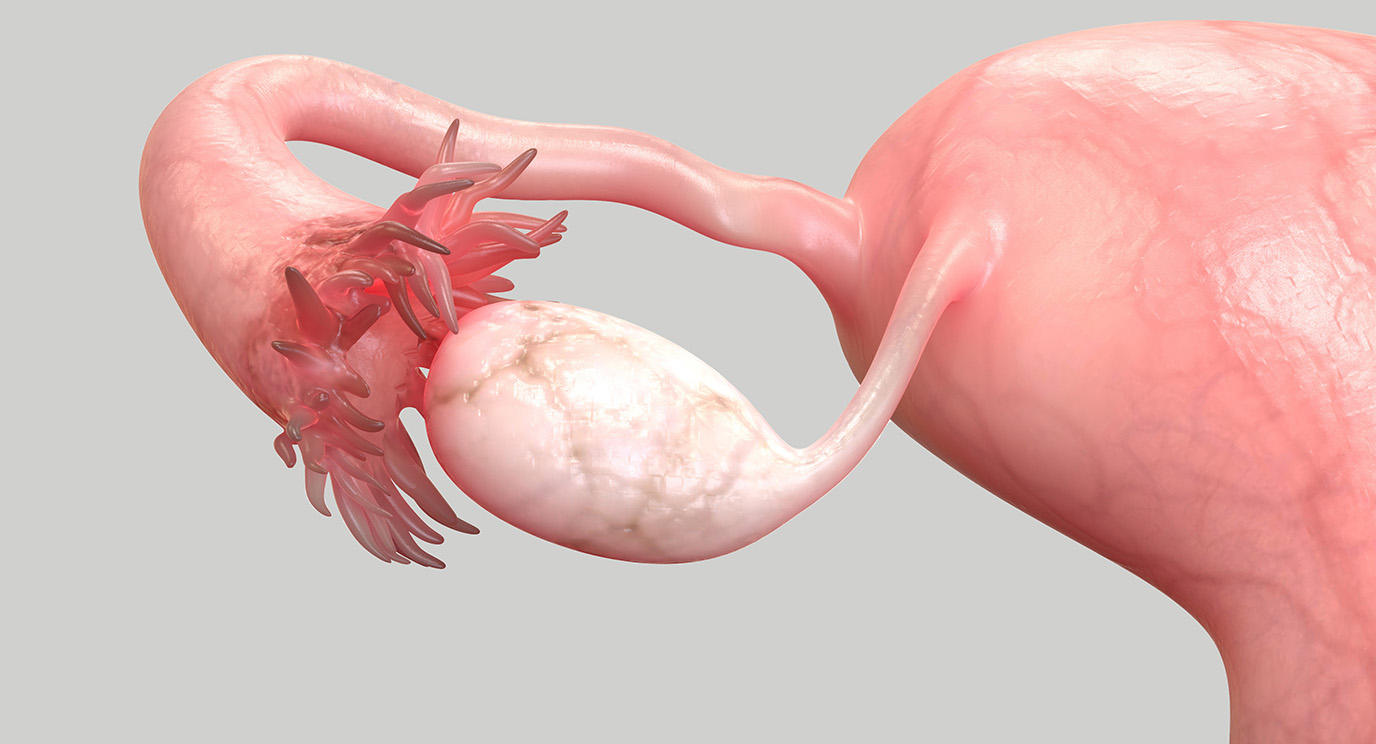

Tubal Blockage Causes Symptoms Treatments Our Approach

Real Fallopian Tube

Real Fallopian Tube